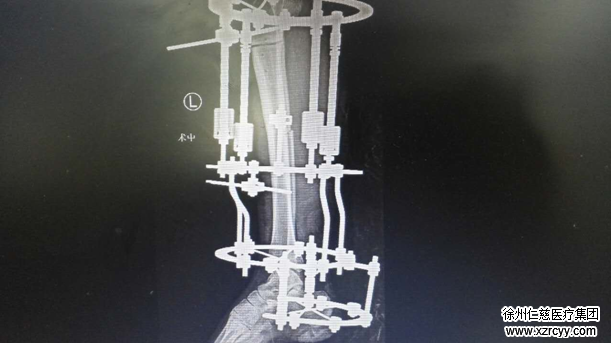

“将左胫腓骨,用特殊的骨刀截断后,在左小腿安装环形外固定架,通过旋动牵引架上的螺丝,截骨处拉开,逐渐延长肢体并矫正内翻畸形! ”徐医生说“每天延长1毫米,病人需要一段康复时间,随后要定期复查,根据病人的血管、神经、骨质愈合情况,来调整肢体延长速度。”

图为肢体延长术中x线片